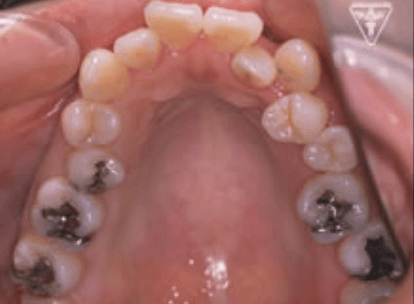

治療前、装置装着直後